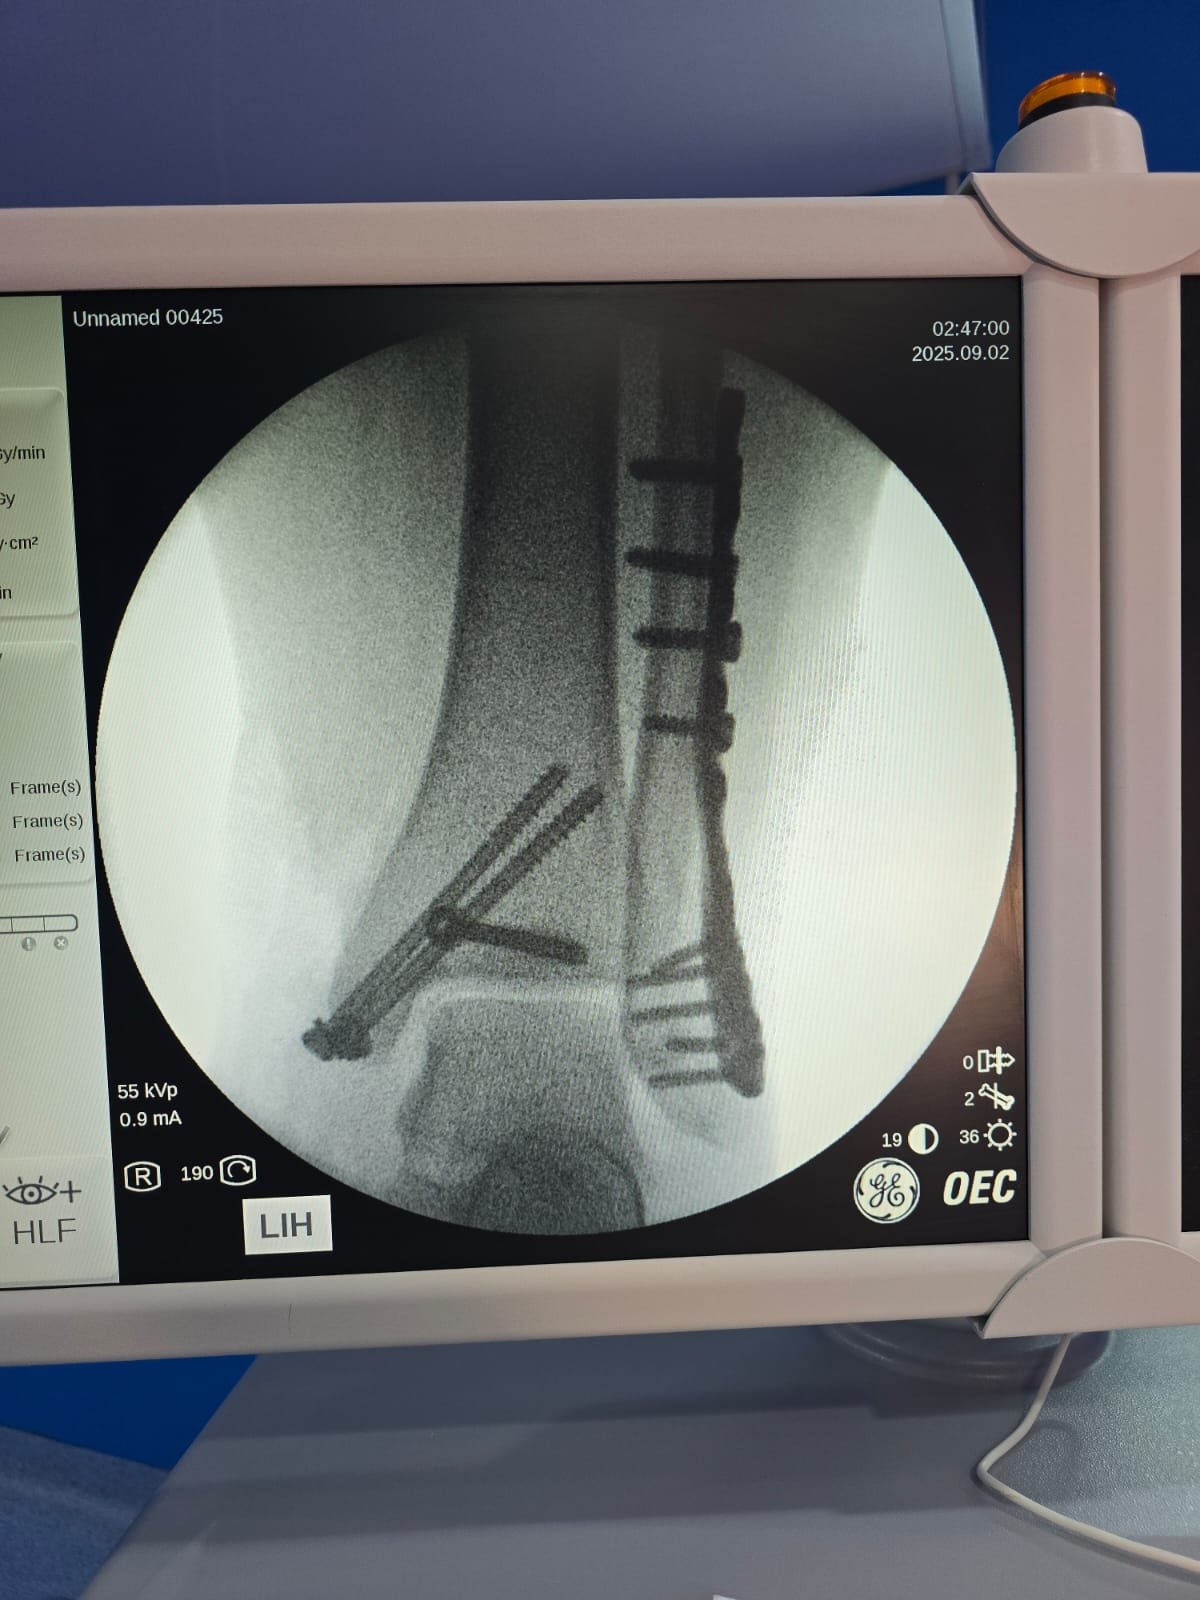

يحدد د. أحمد خطة التعامل مع الكسر أو الرضّ العظمي: فحص سريري وقراءة أشعة، اختيار التثبيت (جبس/جبيرة أو تثبيت جراحي عند اللزوم)، وضبط الألم، ثم متابعة منظمة حتى اكتمال الالتئام.

تشخيص سريع وقراءة أشعة دقيقة في نفس الزيارة.

مواعيد متابعة وصور توثّق تقدّم الالتئام واتخاذ قرار العودة للنشاط.